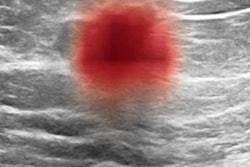

Increased breast density at mammography, defined by the amount of fibroglandular tissue relative to fatty tissue found on images, is a risk factor for developing breast cancer. It can prevent the detection of breast cancer because of its masking effect and cannot distinguish between glandular and fibrous tissue.

The researchers looked at data collected from 8,483 women between 2012 and 2015 with no prior history of breast cancer and an average age of 49 years old. The women underwent breast ultrasound and had dense breasts with negative previous findings from mammography. Out of the total number, 137 women developed breast cancer over a median follow-up time of 5.3 years.